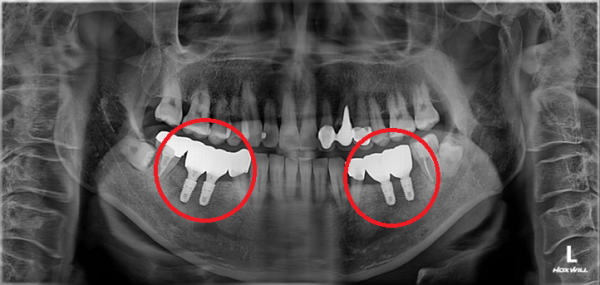

임플란트 양쪽 어금니 임플란트 치료 #2

치주질환으로 인해 치아가 흔들리고

더 이상 사용할수 없어 발치를 해야하는 상태로 내원을 하셨습니다.

임플란트 양쪽으로 총 4개를 식립하여

다시 식사가 가능한 상태로 치료를 마무리 하였습니다.

촬영시기 : 22.03.29(전), 22.10.11(후)